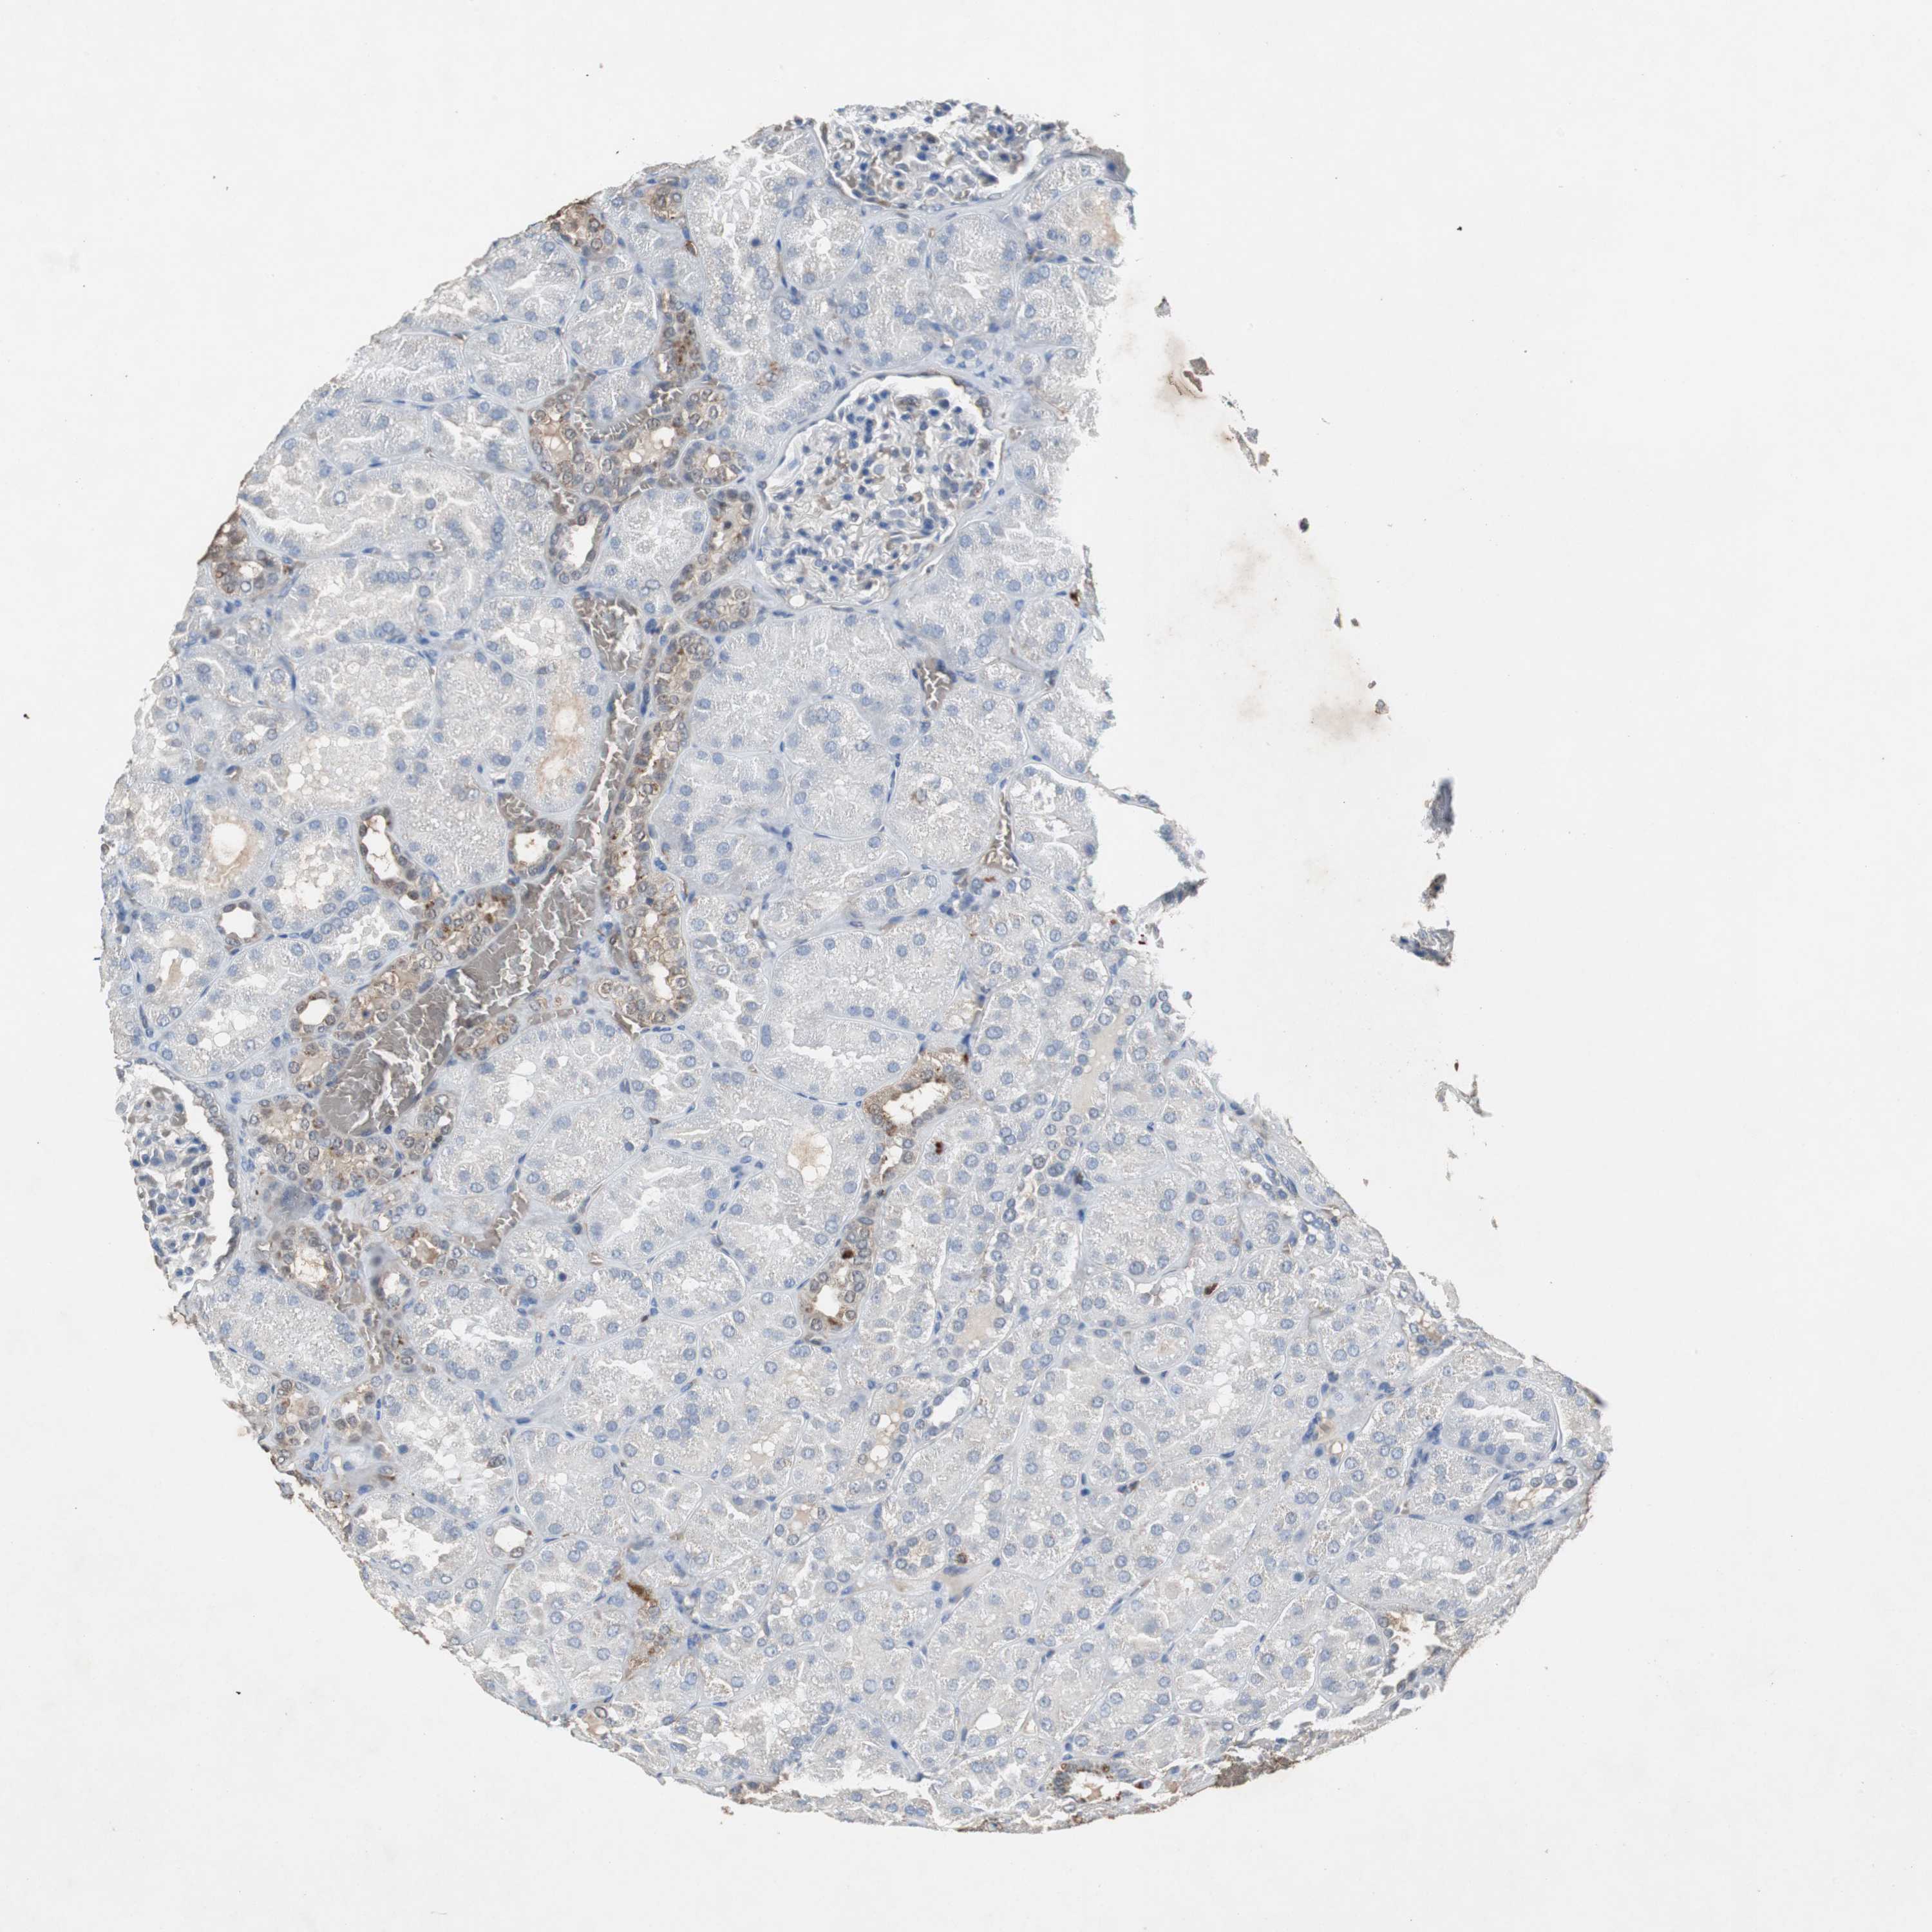

KIDNEY - Antibody stainingi

Antibody staining in the annotated cell types in the current human tissue is reported as not detected, low, medium, or high, based on conventional immunohistochemistry profiling in selected tissues. This score is based on the combination of the staining intensity and fraction of stained cells.

Each image is clickable and will lead to virtual microscopy that enables deeper exploration of all samples and also displays staining intensity scores, fraction scores and subcellular localization as well as patient and tissue information for each sample.

Antibody HPA007305Antibody HPA007306Antibody CAB000106

Cells in glomeruli Not detectedNot detectedNot detected

Cells in tubules MediumMediumNot detected